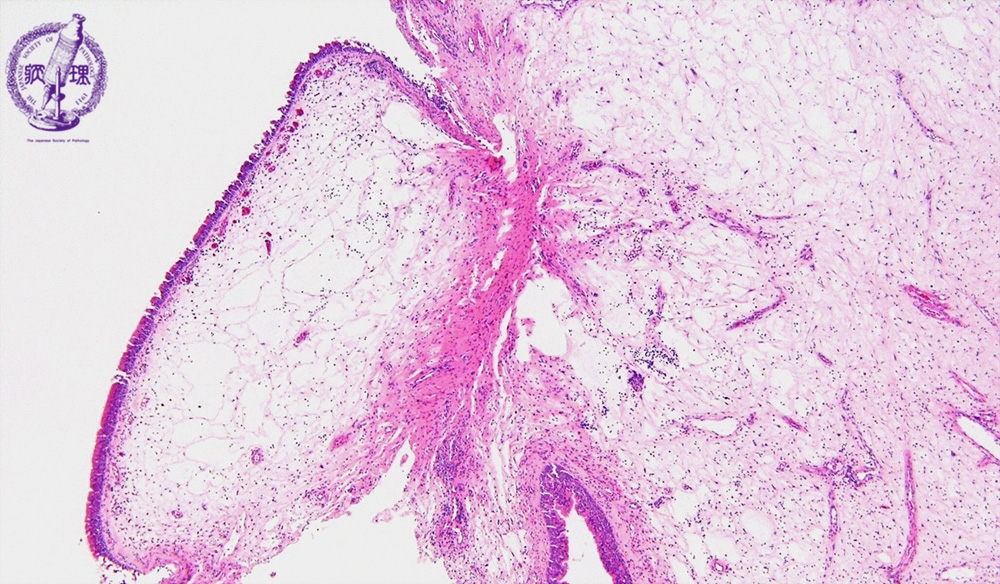

Microscopic view (intermediate power view): Ciliated columnar epithelium lines the mucosal surface, and marked edema and chronic inflammation are observed in the stroma.